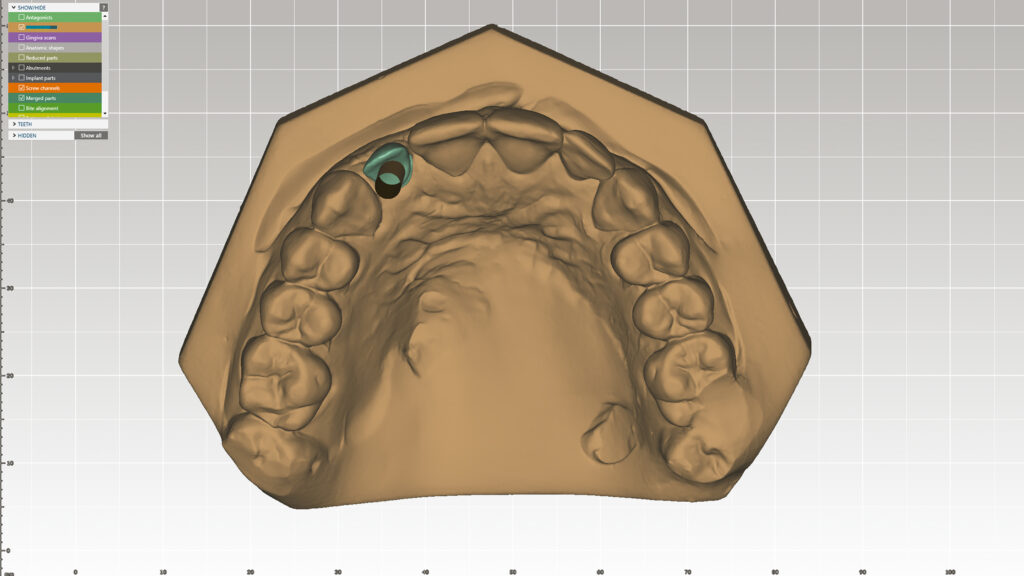

Digitales Set-up (DTX Studio)

Nachdem Zahn 12 auf dem gedruckten Modell entfernt worden ist, kann das Modell mit dem Laborscanner (KaVo LS3) digitalisiert und ein Design-Setup am Bildschirm konstruiert werden (Abb. 8). Die Software-Bibliothek bietet eine breite Auswahl an Zähne in verschiedenen Formen sowie Größen und erlaubt eine Zahnaufstellung in optimaler Position (Abb. 9 und 10). Diese Vorgehensweise spart Zeit und ermöglicht noch mehr ästhetische Kreativität. Der KaVo LS3-Desktop-Scanner ist für die Planung von Implantatversorgungen mit DTX Studio verbunden. DTX Studio ist eine digitale Plattform, die Diagnose und Behandlung verbindet und die Kommunikation im Behandlungsteam optimiert.